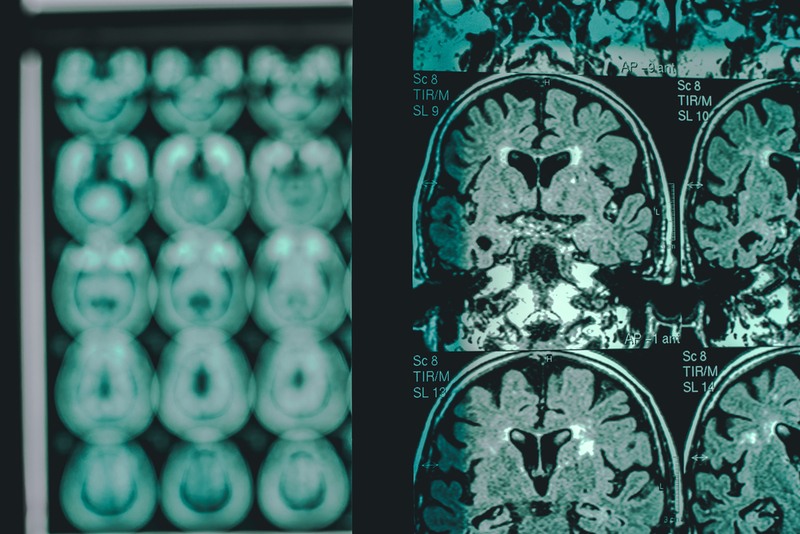

The immune system in the body has an important component called the `complement system’. This is involved in immune surveillance. It is important that it is regulated properly. Otherwise, it can damage the cells of the host’s body itself. This problem is linked to several diseases, including Alzheimer’s, stroke, age-related macular degeneration, asthma, rheumatoid arthritis and cancer.

Understanding the nuts and bolts of how the two mechanisms operate could help gain useful insights into what goes wrong in diseases linked to inappropriate regulation of the complement system, and could consequently help design improved strategies for therapeutic interventions.

These findings have important implications since such a regulatory protein with dual-activity could serve as a lead molecule for developing RCA-based therapeutics for treating pathological conditions associated with faulty regulation of the complement system. Interestingly, DCP was found to be a more efficient inhibitor of the complement system than a molecule called CR1 inhibitor that is currently under clinical trials and which was developed from another protein of the RCA family by a different group. This further strengthens the promise shown by DCP as a potential therapeutic lead molecule.